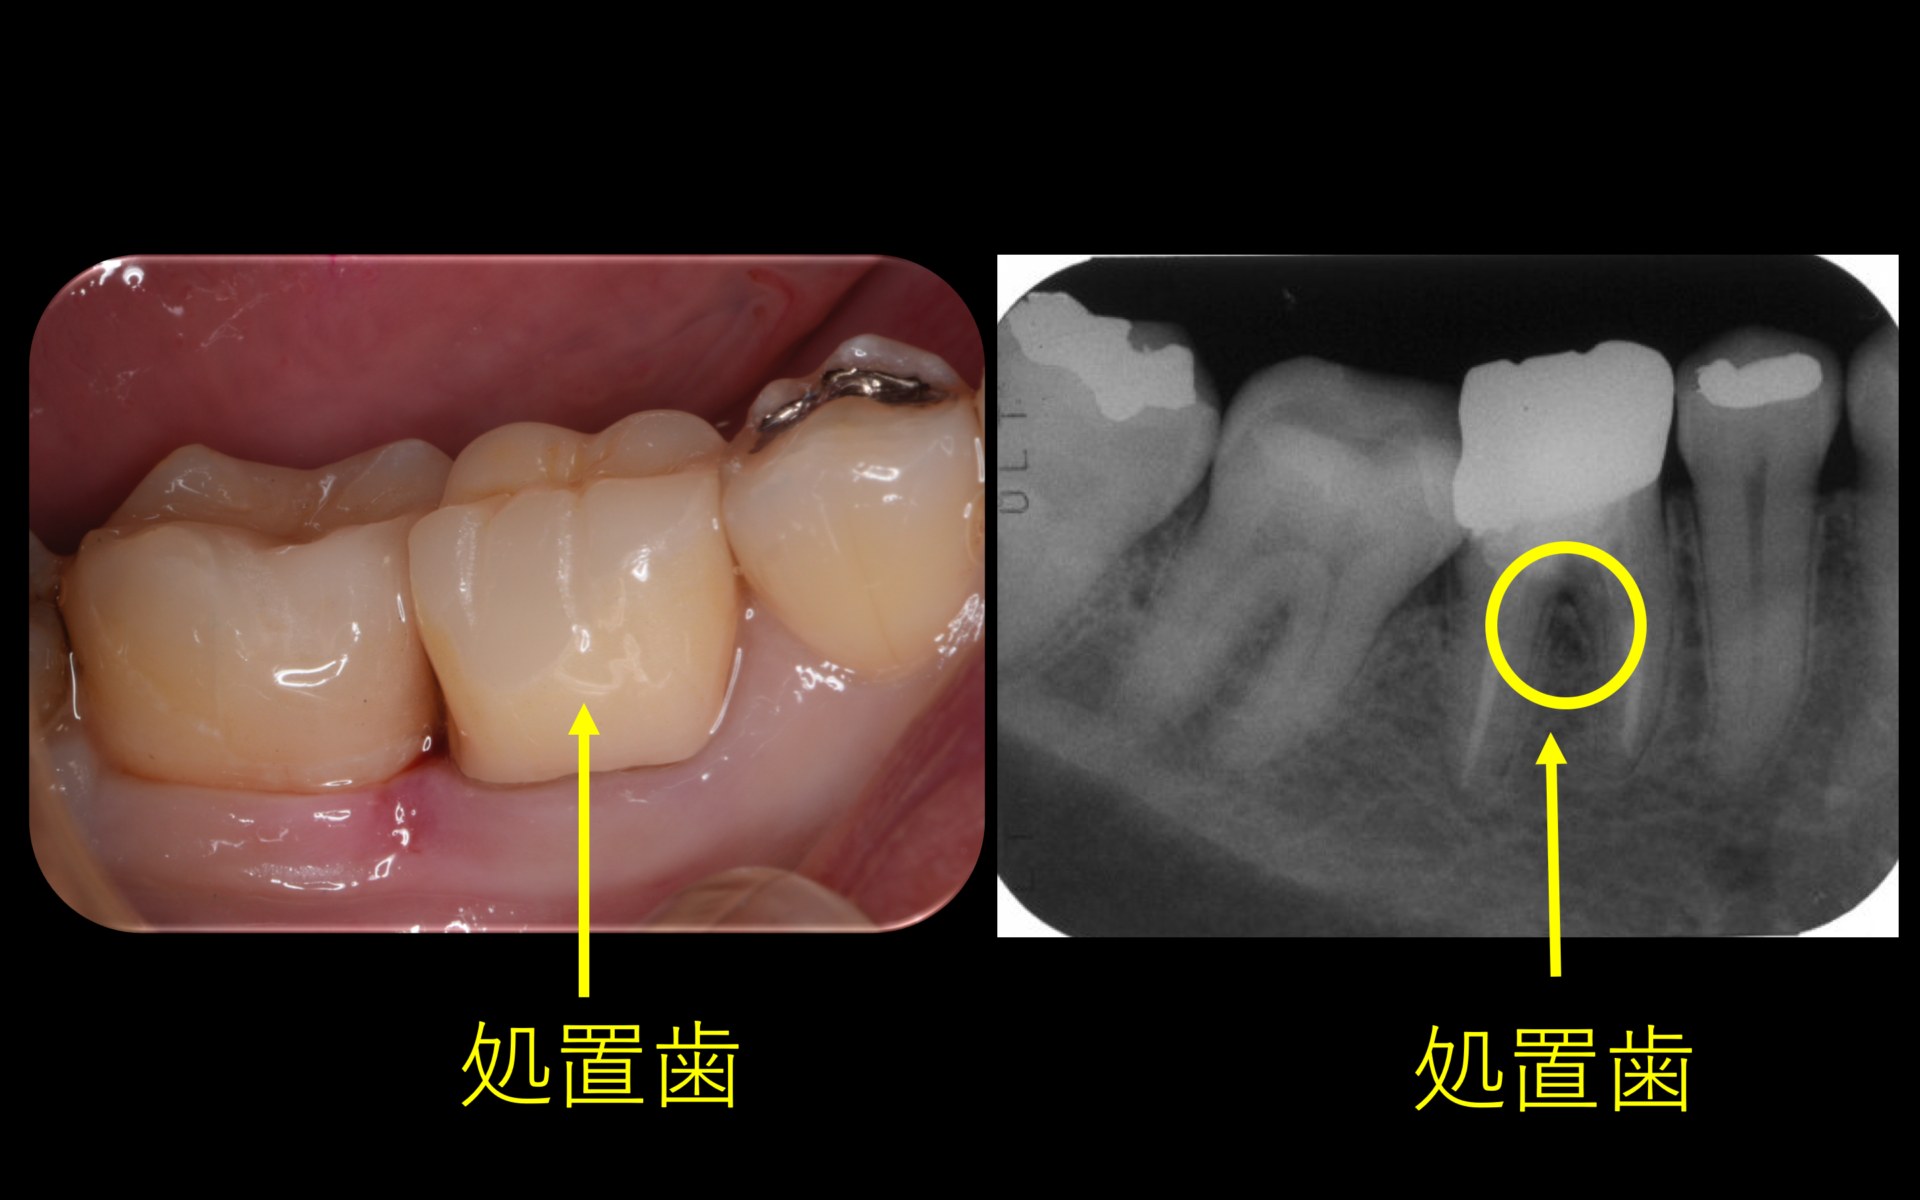

初診時。マイクロスコープで歯肉が腫れているの確認(左図)。レントゲン所見より、黒い部分が腫れている原因の病変である(右図)

術後1年。レントゲン所見より黒い部分(病変)か消失し、完全に骨が再生されている(右図)被せ物はフルジルコニアクラウン(左図)